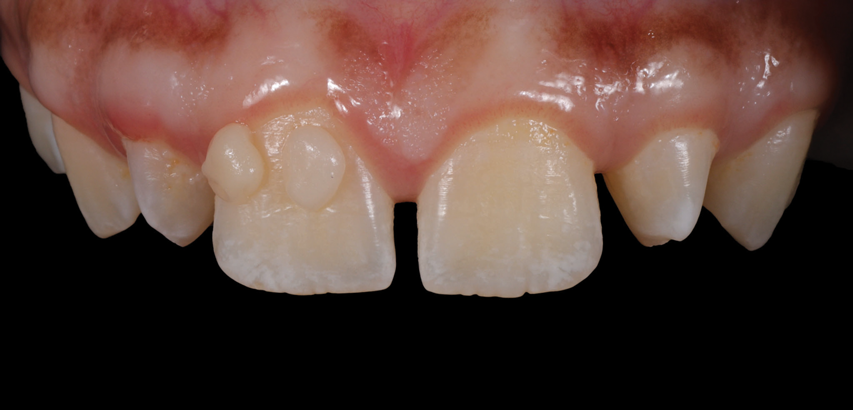

(1.) Pretreatment smile, left lateral smile, and right lateral smile photographs, respectively, showing the patient’s peg-shaped lateral incisors.

Figure 1

(2.) Pretreatment smile, left lateral smile, and right lateral smile photographs, respectively, showing the patient’s peg-shaped lateral incisors.

Figure 2

A 16-year-old female patient presented with the chief complaint that she was dissatisfied with the appearance of her anomalous maxillary lateral incisors (teeth Nos. 7 and 10) and multiple diastemas (Figure 1 through Figure 4). She had been referred for restorative treatment after an initial consultation with the orthodontist. Her first restorative appointment was dedicated to data collection, which included a health history and physical examination as well as the acquisition of photographs (facial, dentofacial, dental), videos (chief complaint, F sound, S sound), vinyl polysiloxane (VPS) impressions, a panoramic radiograph, a bite registration, and a facebow registration. The clinical examination revealed that both of the patient's maxillary lateral incisors were peg-shaped. After a discussion about the risks and benefits of different treatment options, such as direct composite restoration, indirect composite veneers, and porcelain laminate veneers, she chose to have her maxillary lateral incisors treated with direct composite buildup restorations. The index cutback technique was chosen for this case instead of a freehand technique in order to create a new shape according to an ideal wax-up but also to be able to control the thickness of the enamel layer.7